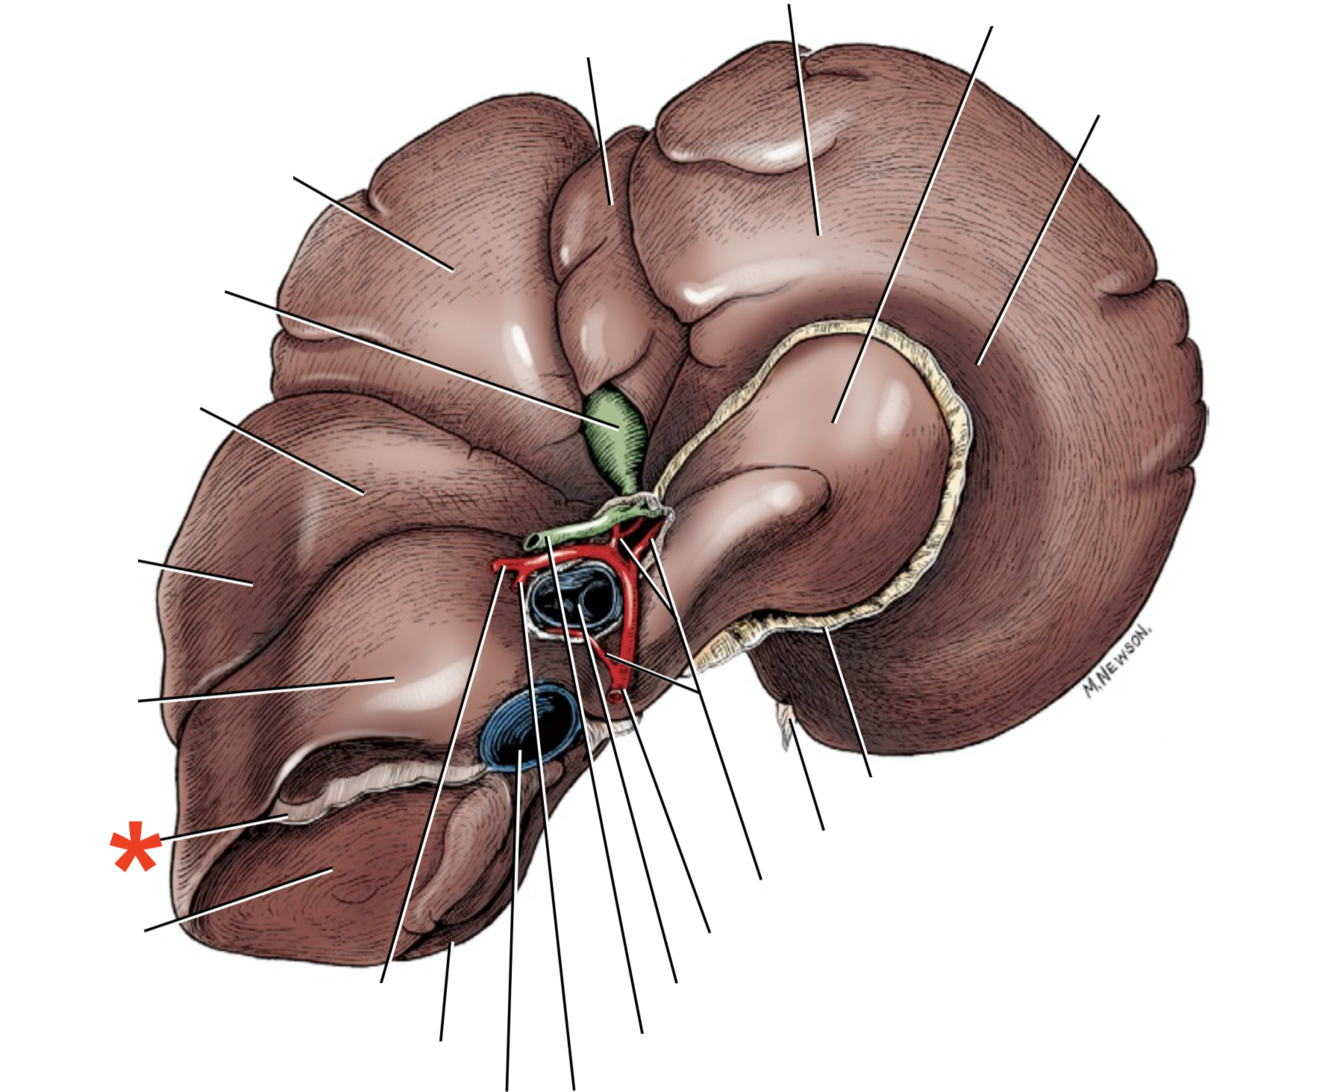

Porta hepatis

- With v. portae et a. hepatica

Lobus caudatus

Lobus quadratus

Lobus hepatis sinister medialis

Lobus hepatis dexter medialis

Lobus hepatis dexter lateralis

Proc. caudatus

V. portae

Proc. papillaris

Lobus hepatis sinister lateralis

Impressio renalis

Liver of a Cat

Fascies visceralis

Dorsal Aspect

Area nuda

- Not covered by serous membrane